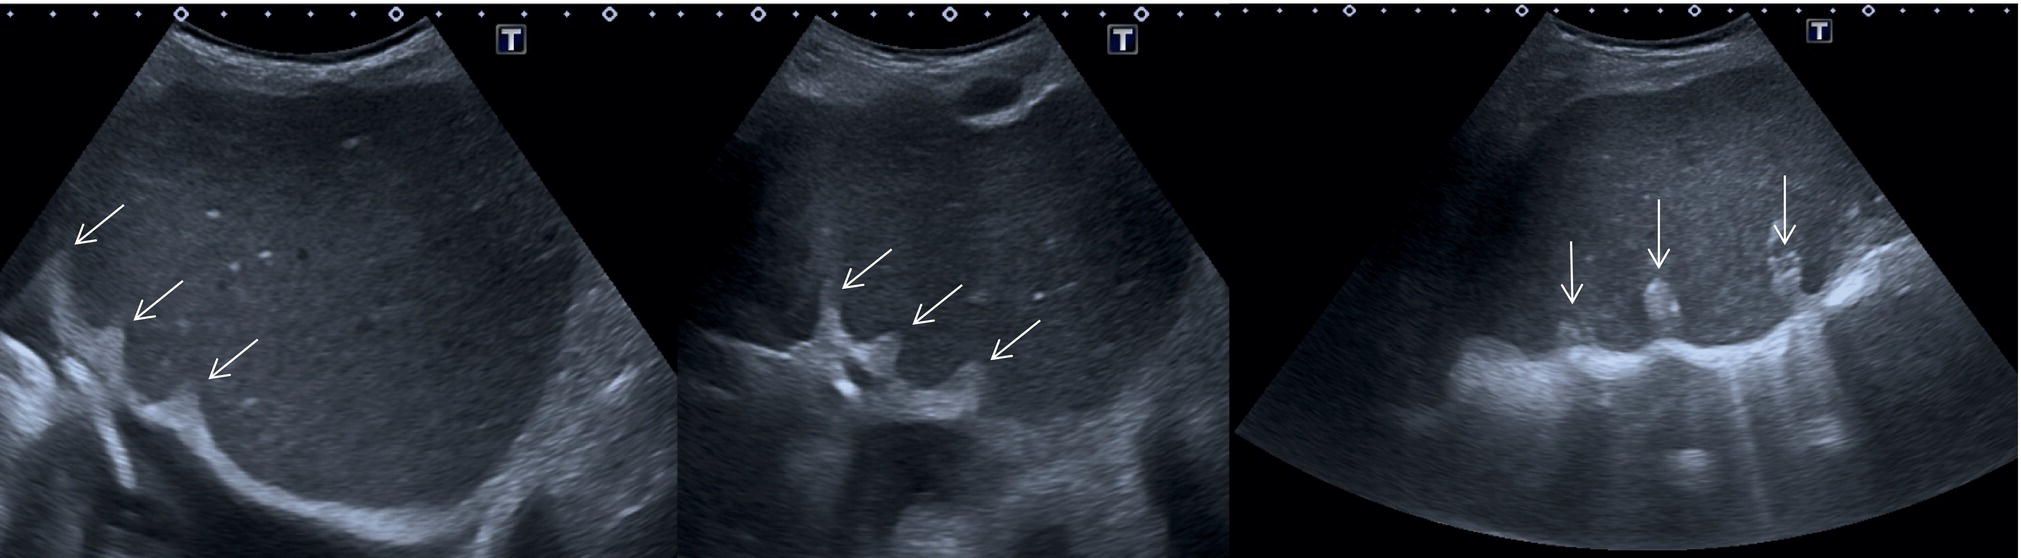

Normal Variants of Liver Anatomy

Liver anatomical variants might be related to the shape, size, and vasculature, as well as the GB and biliary tree. Parenchymal variants include diaphragmatic slips, sliver of liver, Riedel’s lobe, and papillary process of the caudate lobe [5]. Diaphragmatic slips represent incomplete accessory fissures at the site of the diaphragmatic liver surface due to invagination of the diaphragm (Figure 3.16). A sliver of the liver refers to an anatomical variant where the left liver lobe extends to the left hypochondrium, wrapping around part of the spleen (Figure 3.17). Another common variant is a Riedel’s lobe, represented by a downward tongue‐like projection of the lower anterior edge of the right liver lobe (segment VI), sometimes so pronounced as to extend along the right paracolic space up to the iliac fossa (Figure 3.18) [6]. The papillary process is an anterior and medial extension of the caudate lobe, which might resemble a lymph node or mass next to the pancreatic head or IVC (Figure 3.19).